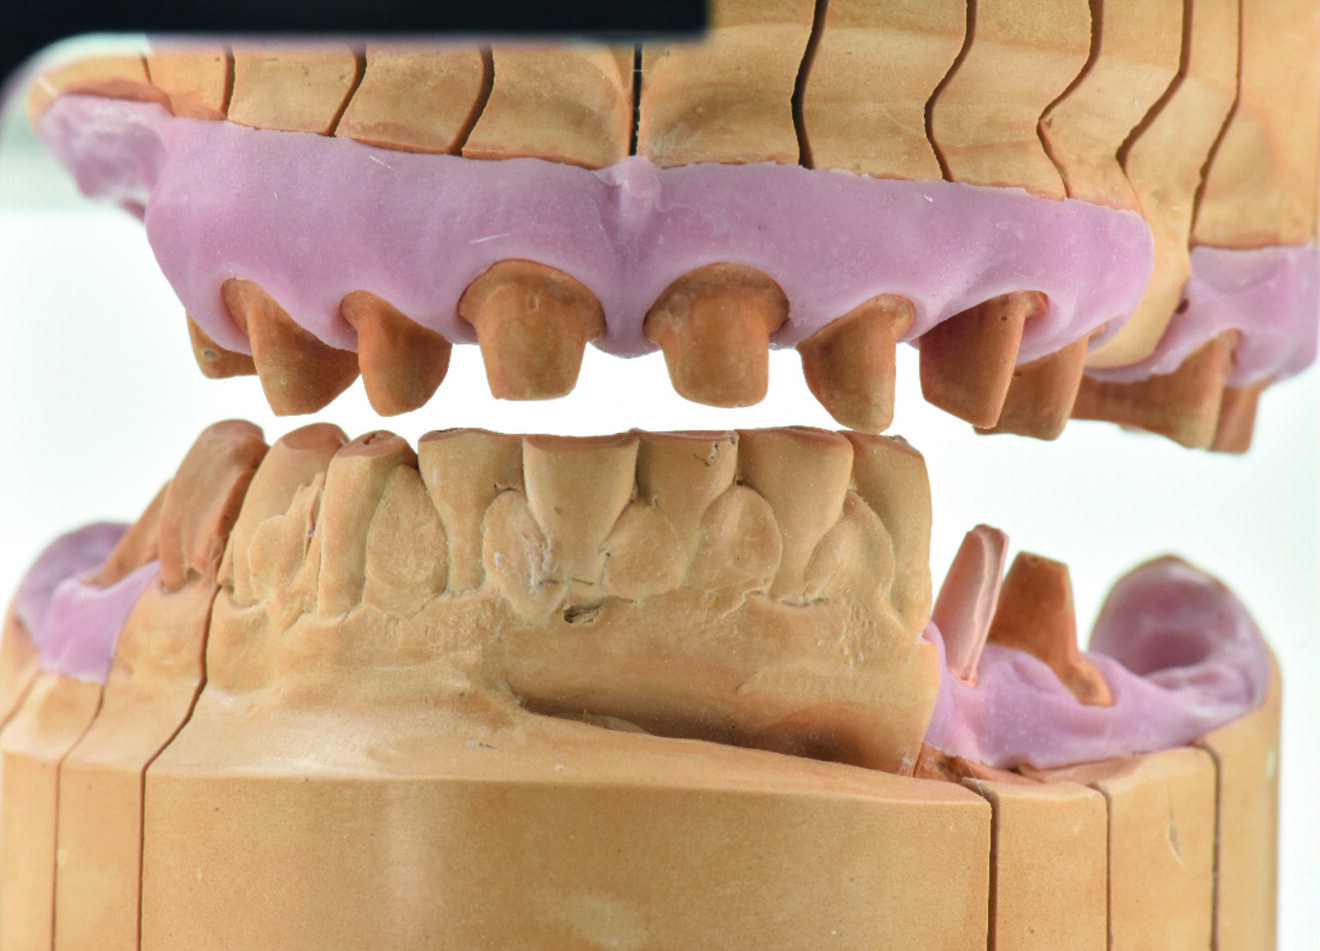

Une patiente de 50 ans atteinte d’une péri-implantite à un stade avancé, s’est présentée à notre laboratoire avec le souhait d’une restauration fonctionnelle et esthétique (Figs. 2a et b). Nous avons établi un plan de traitement qui consistait à traiter la péri-implantite, à poser de nouveaux implants et, finalement, à améliorer l’esthétique générale. Notre première étape a été de reconstruire complètement l’occlusion par une restauration en zircone Zolid FX Multilayer (Amann Girrbach), sauf pour les dents antérieures inférieures.

Une telle reconstruction requiert le plus grand nombre d’informations possible sur la patiente. Nous avons donc utilisé le système d’axiographie CADIAX (GAMMA Medizinischwissenschaftliche Fortbildungs-GmbH) pour obtenir les données sur les mouvements de l’articulation. Les données de transfert de l’arc facial, combinées à celles de l’articulateur Artex CR (Amann Girrbach) et du système CADIAX, sont nécessaires pour reproduire les mouvements mandibulaires avec l’articulateur virtuel (Figs. 3a et b).

Durant la conception, je me concentre sur quelques éléments clés, que je vérifie ensuite sur l’articulateur virtuel. Les paramètres les plus importants sont les surfaces d’appui occlusales, telles que celles des dents postérieures, qui sont essentielles pour la stabilité des contacts en intercuspidie et de la dimension verticale. Ces surfaces protègent l’articulation contre la compression et les dents antérieures contre les contraintes excessives.